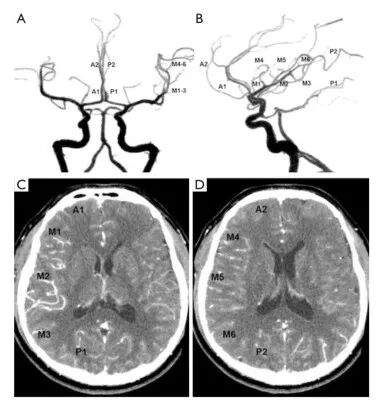

根据阿尔伯塔卒中规划早期CT评分(Alberta Stroke Programme Early CT Score)将大脑半球分为10个解剖区域。采用美国介入和治疗神经放射学会/介入放射学会(American Society of Interventional and Therapeutic Neuroradiology/Society of Interventional Radiology,ASITN/SIR)提出的侧枝代偿0-4级的5级法分级,由两位神经影像学医生通过DSA图像对10个解剖区域的侧枝代偿程度进行评级:0级,缺血区域无侧枝代偿;1级,缺血区域周围有缓慢发展的侧枝代偿,无灌注区;2级,缺血区域周边快速发展的侧枝代偿,无灌注区;3级,缺血区域侧枝代偿发展缓慢,静脉期可见血管显影;4级,侧枝代偿充分,并经逆行灌注至整个缺血区。由另两位神经影像学医生对10个区域CTP-Sis进行分级:0级,动脉期和静脉期缺血区均无增强;1级,缺血区边缘静脉期增强;2级,缺血区边缘动脉期增强,而静脉期有无灌注区;3级,缺血区静脉期完全增强;4级,缺血区动脉期完全增强(图2、3)。

24例症状性单侧MMD患者中,男15例,女9例;平均年龄30.7±10.1岁;MMD于左侧17例,右侧7例。CTP与DSA间隔时间为14.7±10.3天。侧枝代偿5级法分级结果,按CTP-Sis分级法:0~4级分别为2、22、18、73、125个和按DSA分级1、17、11、86、125个。CTP-Sis分级低估DSA分级的部分3级区域(表1、图4)。两位DSA读片者结论基本一致,两位CTP读片者结论亦基本一致。

图4. 侧枝代偿两种分级比较。22岁男性单侧烟雾病患者。双侧颈内动脉DSA的动脉期(A)和静脉期(B),显示右侧大脑中动脉延时显影(箭头,M1-6,3级);CTP-Sis分级:动脉期(C)中度强化(M1-6),静脉期(D)完全强化。白色箭头表示低灌注区域。患者侧枝代偿两种分级结果一致。

该研究建立评估侧枝代偿的CTP-Sis分级系统。CTP原始图像可以提供类似DSA的动脉期、实质期和静脉期的图像;根据侧枝循环到达缺血区的速度和程度进行分级,与DSA分级有较高的一致性。由于CTP-Sis分级侧重于软脑膜侧枝代偿,可能因存在皮质下白质病变或梗死,所以对某些DSA分级为3级的区域评分偏低。